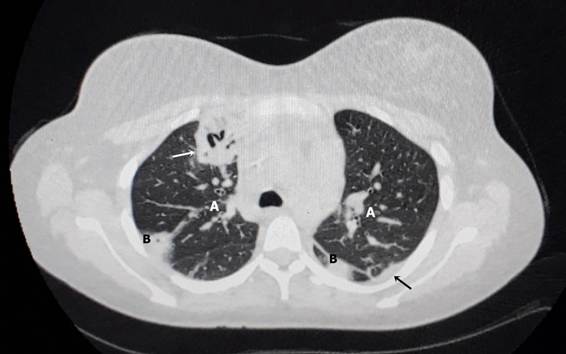

Apesar da resolução do quadro infeccioso local e da melhora clínica inicial, a paciente evoluiu, ainda durante a internação, com tosse seca persistente, dor torácica, febre vespertina e dispneia em repouso. Uma tomografia computadorizada de tórax com contraste revelou metástases nodulares pulmonares e pleurais bilaterais, derrame pleural à direita, caverna pulmonar e alterações do parênquima compatíveis com tuberculose pulmonar (Figura 3). A hipótese diagnóstica foi confirmada clinicamente em conjunto com o resultado do exame de baciloscopia direta de escarro (BAAR) com resultado positivo (3+) e por exame de imagem.

Figura 3. Tomografia de tórax: A) nódulos metastáticos difusos em janela pulmonar; B) nódulos pleurais, caverna tuberculosa (seta branca) e derrame pleural (seta preta)